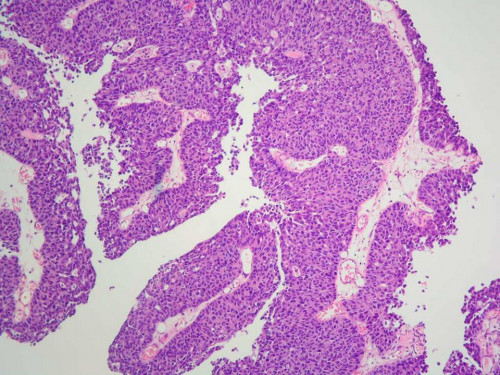

Die damals durchgeführte bioptische Untersuchung ergab folgendes Ergebnis: pTa,

G1.